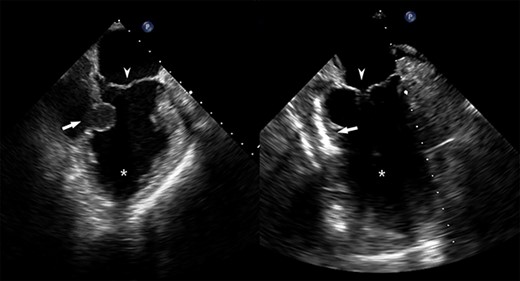

He returned 5 weeks later complaining of 72 hours of malaise, fevers and chest pressure. He was tachycardic and hypotensive but intermittently responsive to fluid resuscitation. He noted reluctance to present for evaluation, given concerns regarding COVID-19 exposure if he was hospitalized. A computed tomography (CT) of the chest noted a left ventricular irregularity and adjacent thrombus (Fig. 1). Echocardiography revealed an ejection fraction of 35%, a large pericardial effusion and an aneurysmal-appearing inferolateral left ventricular wall with intrapericardial thrombus (Fig. 2).

Pre- and post-repair transesophageal echocardiography images; leftward image: asterisk = left ventricular cavity, arrow = ventricular wall defect, arrowhead = mitral valve; rightward image: asterisk = left ventricular cavity, arrow = ventricular wall patch closure, arrowhead = mitral valve.

Emergent surgical intervention was performed with a median sternotomy, aorto-bicaval cannulation and antegrade cardioplegia. Dense intrapericardial adhesions were lysed, revealing a large pseudoaneurysm sac containing murky, seropurulent fluid. After debridement, a 4-cm defect in the inferolateral wall below the mitral valve was observed (Fig. 3). This was closed with an oversized bovine pericardial patch secured to healthy endocardium with a running polypropylene suture. The pseudoaneurysm edges were re-approximated over the repair in a linear fashion using two layers of suture polypropylene buttressed with felt strips. Post-repair echocardiography demonstrated no residual defect, ventricular geometry distortions or mitral valvular dysfunction (Fig. 2).